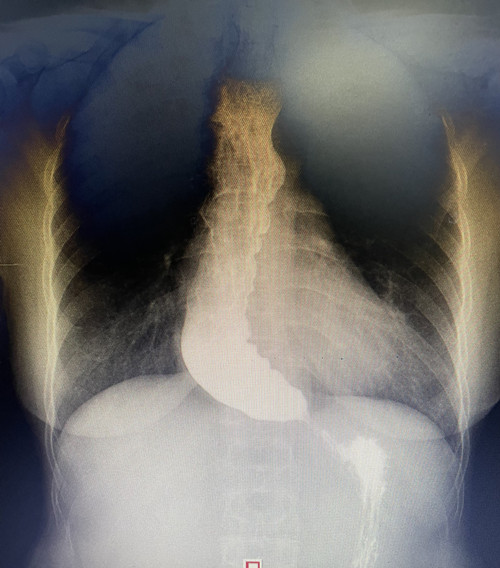

近日,消化内科二病室先后入住了两位患者,因为“进食哽咽感”来寻求治疗。想吃东西,胃“不开门”,怎么办?两位患者入住后做了消化道钡餐检查,结果显示“食管下段呈鸟嘴样改变”,确诊为贲门失迟缓症。确诊后,吴明浩主任为患者进行POEM手术——切开食管环状肌,为患者打开食管与胃的“大门”,以达到缓解症状的效果。手术两天后,患者开始逐渐进食,“我现在能一次性吃下一碗粥都不会觉得堵了”一位患者术后开心地告诉护士,比起术前,一碗粥药分好几次喝,喝一点就会觉得前胸有梗阻感,现在能顺利进食的感觉太好了。